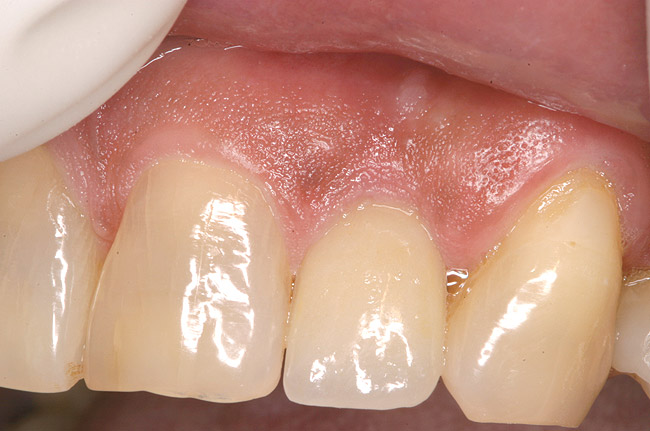

Figure 17 shows a case of advanced recession on the facial of tooth No. 10, which had a periodontal-endodontic lesion. Tooth No. 10 was extracted with an implant placed during the same appointment. As demonstrated in this case (Figure 18 and Figure 19), the facial gingival margin can be moved coronally with immediate implant placement.

Figure 18  Same case as in Figure 17 after extraction of tooth No. 10 and immediate implant placement (Astra Tech, Inc, Waltham, MA) with delayed restoration. Note the significant coronal position of the soft tissue.

Figure 18